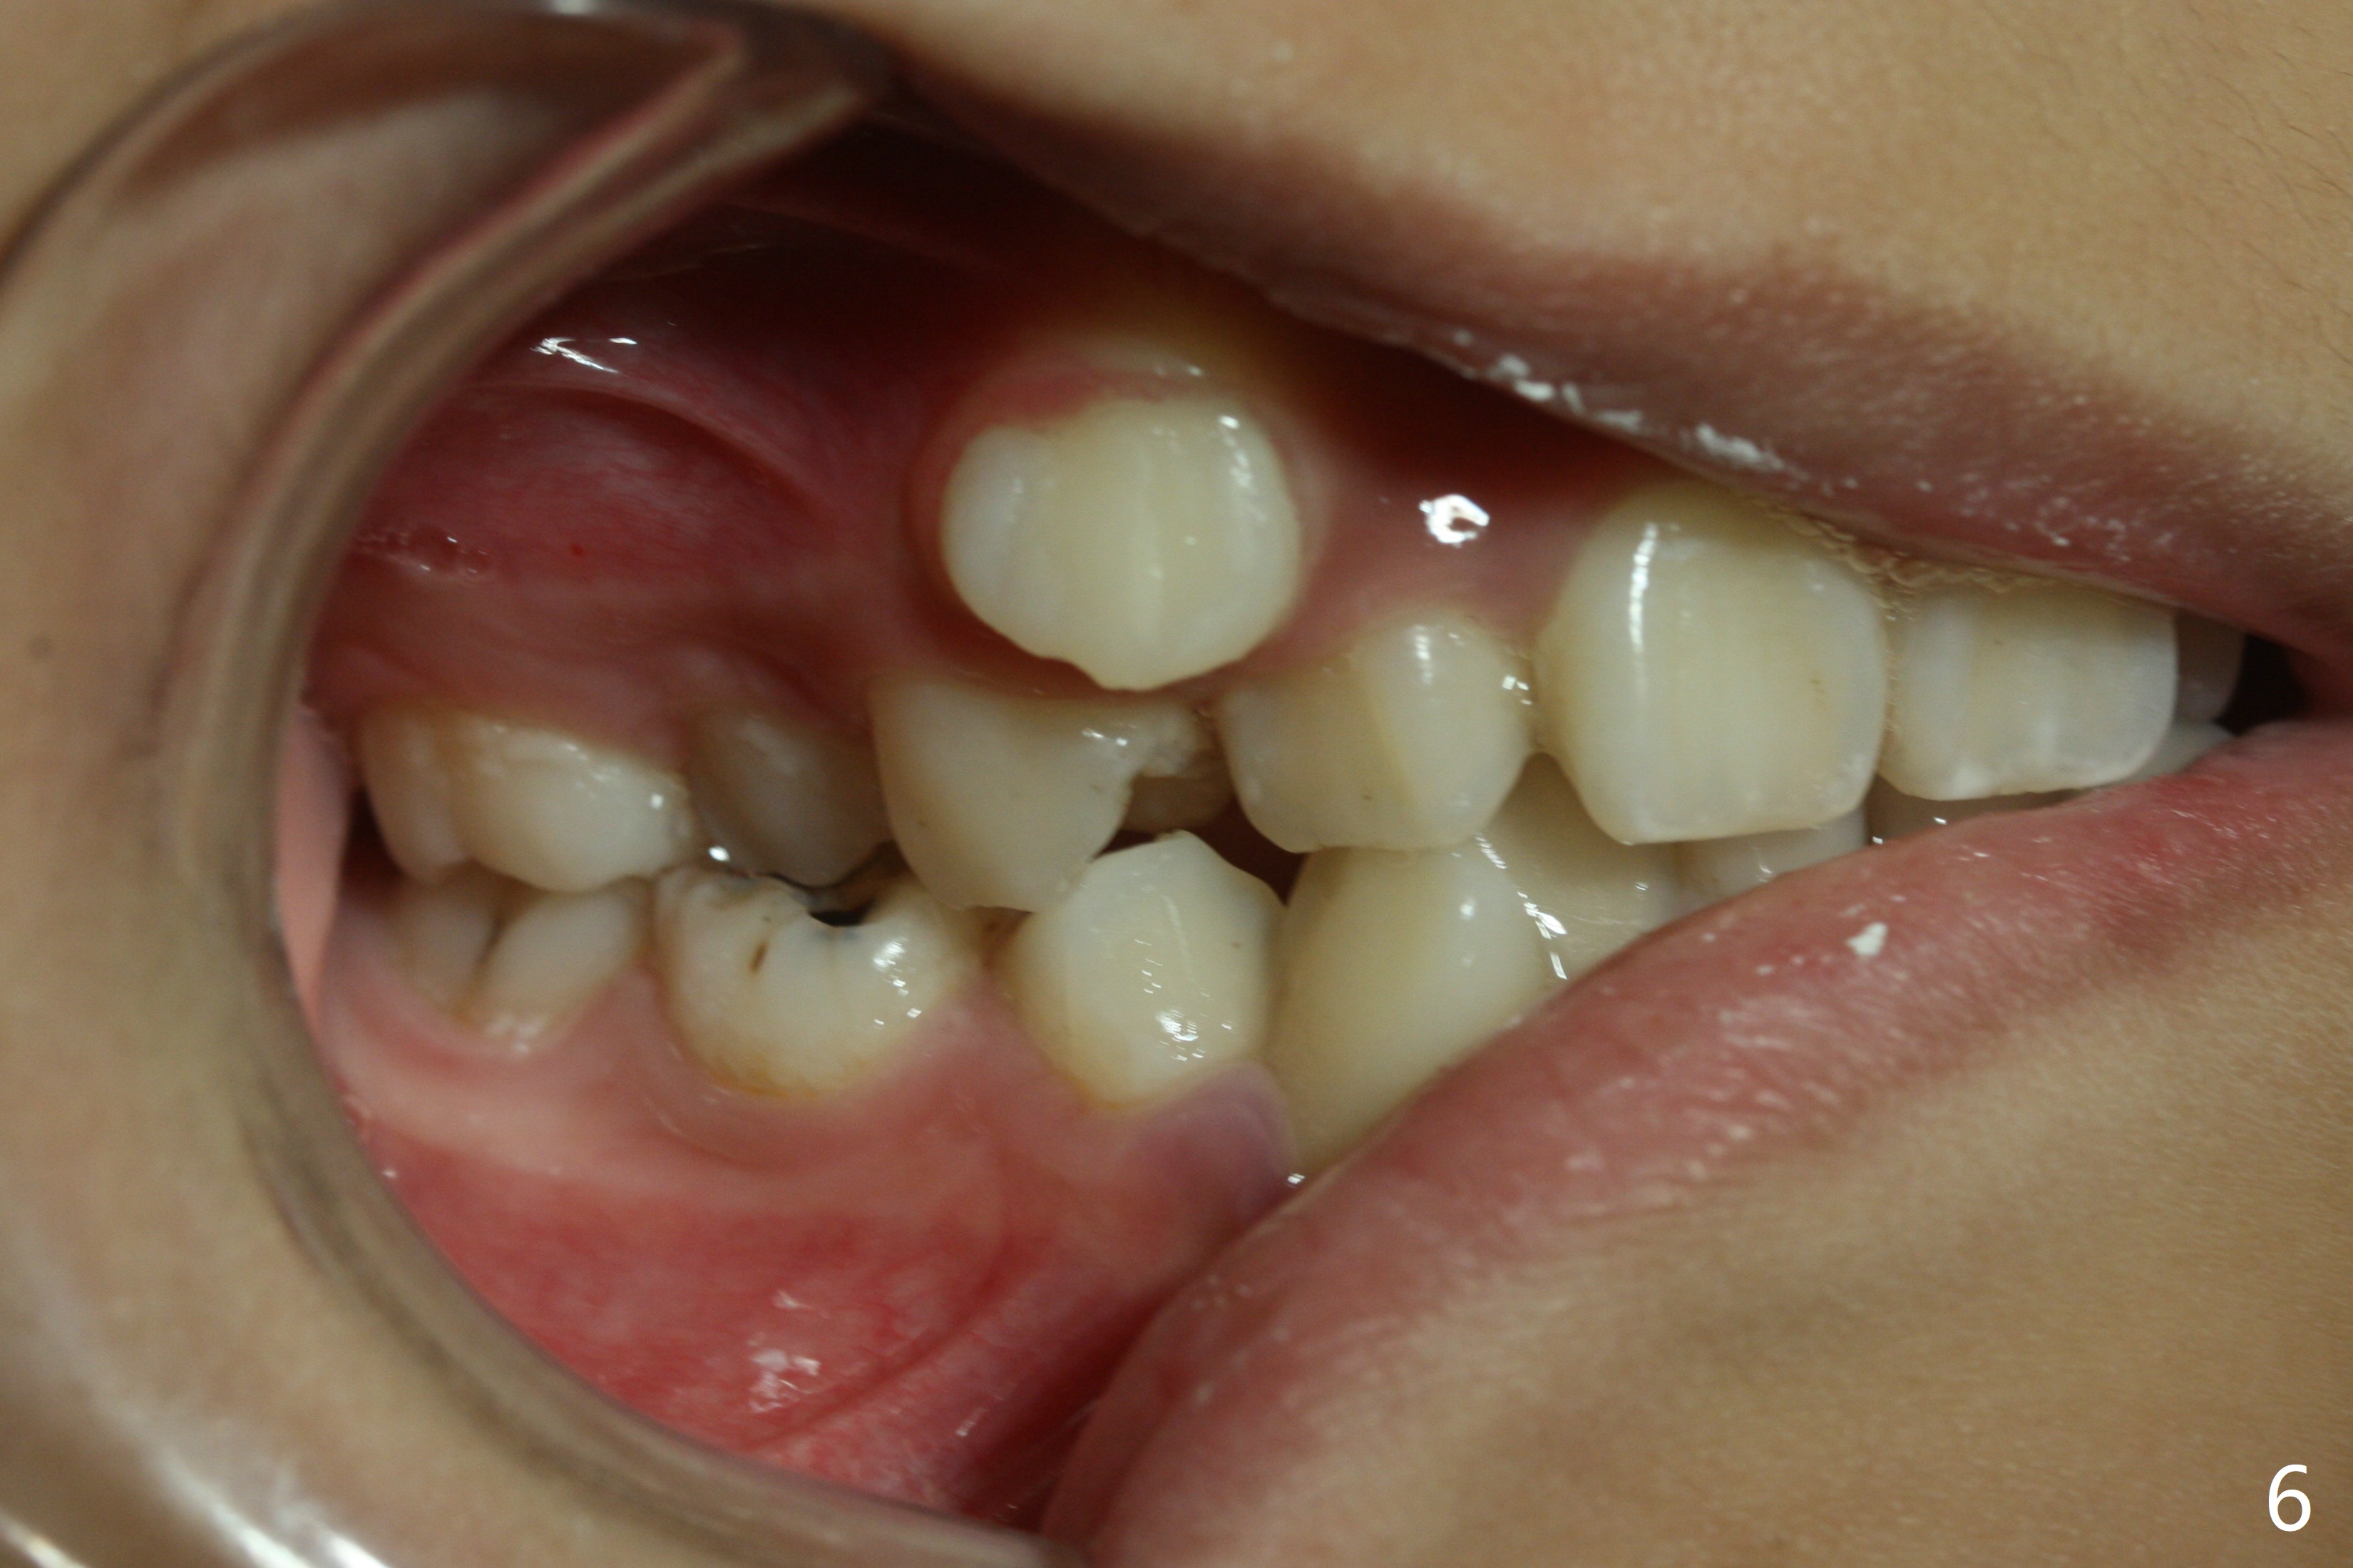

Severe crowding with normal facial profile appears to dictate extraction of 4 bicuspids and of the lower 2nd primary molars (Fig.1-11).  Since there is no time for banding before school, delay in orthodontic treatment post extraction will lose space?

Dear Dr. Shaughnessy: can you open the following link?  I would like to try to extract 4 bicuspids and 2 lower primary 2nd molars and let the canines shift by themselves.  But I wonder whether the 2nd permanent bicuspids, especially the upper ones, may shift mesially instead.  How would you like to handle the situation?

In fact, the family is moving out of state.  To accomplish automatic shifting before seeing a new dentist, extraction is executed.  At the mother's request, six teeth are removed.